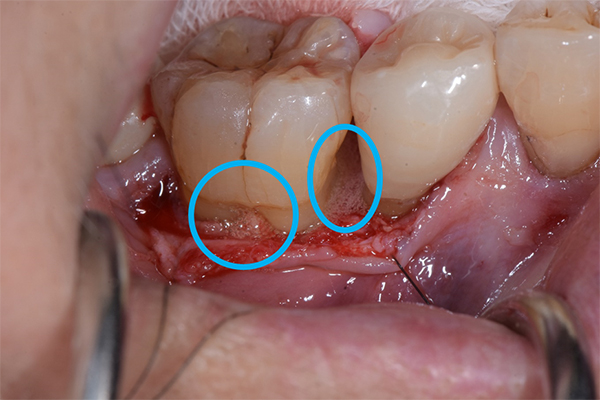

軽度〜中程度レベルの歯周炎であれば、ここで改善が見られますが、中程度以上の歯周炎の場合は、その後に歯周外科処置を行うことが多いです。なぜなら、歯周ポケットが5mm以上ある部位にSRPを行っても多くの歯石の取り残しがあるという報告があるため、深い歯周ポケットを有する患者さんに対しては歯周外科処置を行います。歯周外科処置で一般的な術式は歯肉剥離掻爬術です。痛く無いように麻酔(局所麻酔)をした後、歯肉をメスで切り(切開)、切った歯肉を骨から剥がし(剥離)、歯の根に付着した歯石、歯槽骨の形態などが直接見える状態で、歯石や感染物の除去を行います。その際必要であれば、その後に患者さん自身で清掃がしやすいように骨の形態を整える歯槽骨整形も行います。最後に切った部分を縫って(縫合)処置を終わります。

歯周組織再生療法といい、先に記しました通り、GTR法、エムドゲインを使用した方法、リグロスを使用した方法といくつかあります。GTR(Guided Tissue Regeneration)法とは、歯周外科処置と同様に歯肉をメスで切り(切開)、切った歯肉を骨から剥がし(剥離)、歯の根に付着した歯石、歯槽骨の形態などが直接見える状態で、歯石や感染物の除去を行います。その後、骨が吸収して失われた部分にこのバリア膜で覆い縫って(縫合)処置を終わります。バリア膜で覆うことで、歯肉などの軟組織が骨の中へ直接入り込むことを防ぎ、新しい血管が新生され、歯周組織の再生を促します。治療後およそ6ヶ月待ちます。